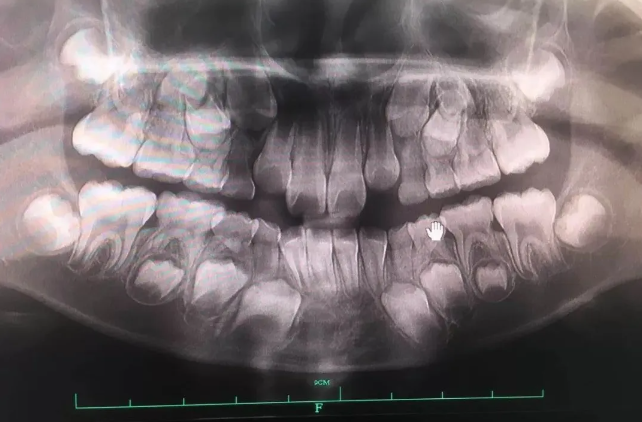

🔎儿童恒牙萌出